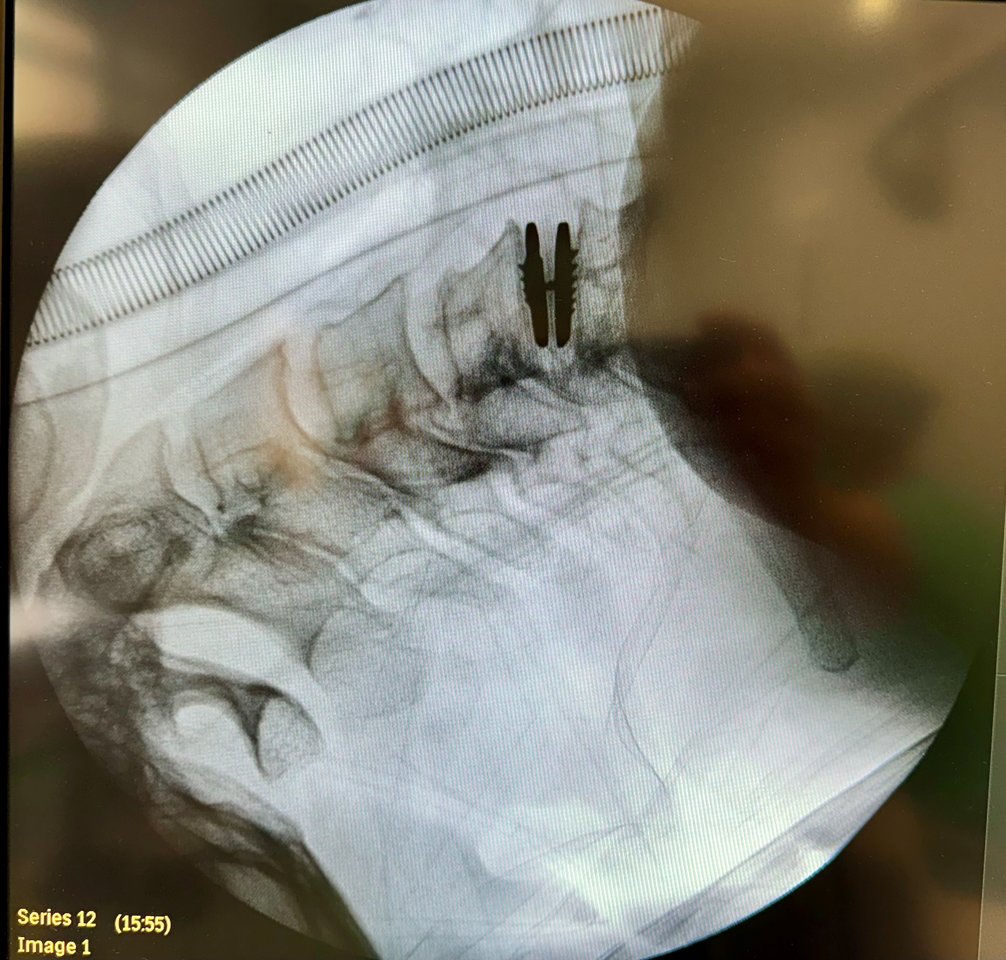

Pasak gydytojo, ši Lietuvoje unikali operacija gali būti taikoma pacientams, besikreipiantiems dėl degeneracinių kaklinės stuburo dalies pakitimų, išvaržų ar susiformavusių stenozių. Per nedidelį pjūvį kaklo priekinėje pusėje, pirmiausiai pašalinamas pakenktas diskas, pašalinamas sustorėjęs raištis ar išvarža, atlaisvinus nervus ir nugaros smegenis – dedamas implantas. Pacientai po operacijos tą pačią dieną gali keltis, vaikščioti, atlikti galvos judesius. Sekančią dieną po operacijos išleidžiami į namus.

Naujieji implantai sudaryti iš trijų dalių, dviejų specialaus metalų lydinio plokštelių ir iš polimero pagamintos šerdies, kurios, saveikaudamos tarpusavyje, geba išlaikyti įprastus stuburo segmento judesius.